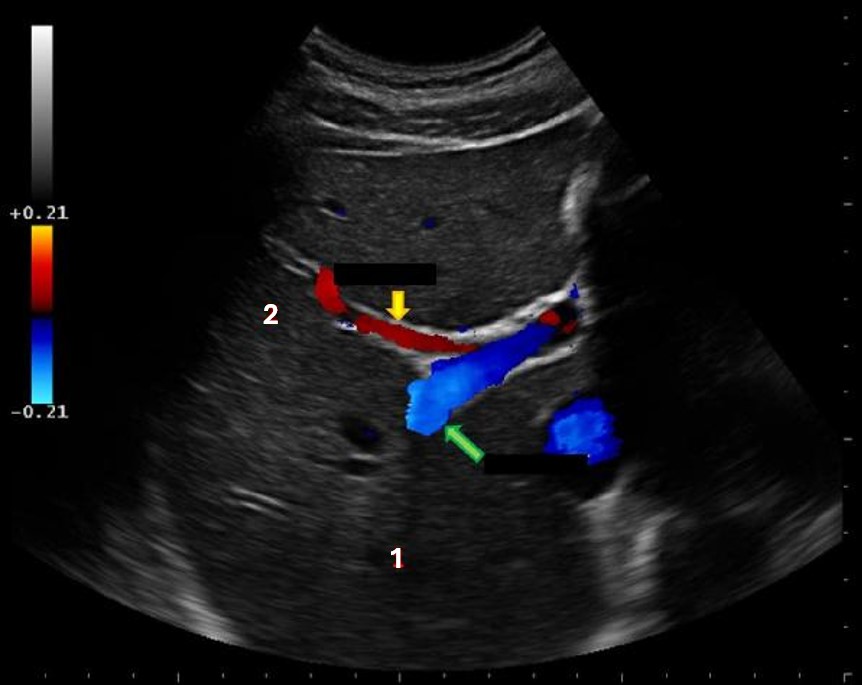

What structure is indicated by the yellow arrow?

main lobar fissure |

What liver vessel is indicated by the green arrow?

posterior right portal vein |

What structure is indicated by the blue arrow?

right portal vein |

What structure is indicated by the green arrow?

Main portal vein |